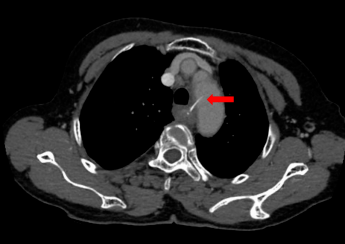

食管异物之"枣核"丨ct表现_手机搜狐网

图片尺寸492x481